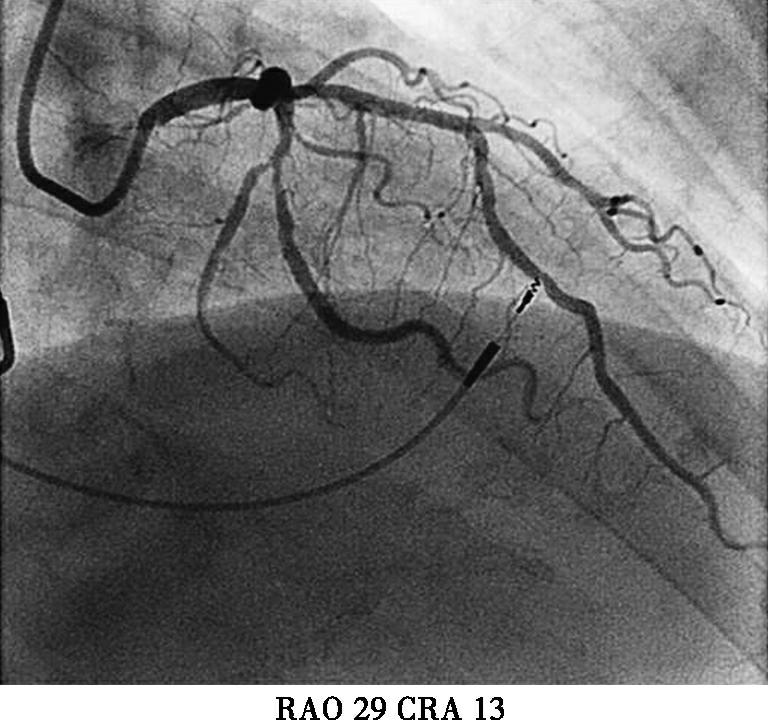

本例患者虽然有高血压、糖尿病等冠心病危险因素。起搏器电极植入后立刻发生的胸痛考虑与心绞痛关系不大,且患者未出现心电导联ST-T变化,胸痛原因主要考虑:起搏电极导致冠脉损伤?起搏电极刺破右室?遂台上决定立即行冠脉造影(图3);多个投照体位均可见起搏电极螺旋尖端触及前降支,因此决定行前降支血管内超声(IVUS)检查,结果于电极接触部位,血管8点钟方向可见强回声,距离血管外膜小于1mm;综合判断起搏电极损伤血管外膜导致胸痛的可能性大;随后进行电极重新植入,并再次造影排除起搏电极穿透冠脉可能,电极具体位置及冠脉造影见图4,心室起搏参数(阈值0.8V,阻抗670Ω,R波10.0mv)。患者症状完全消失,于导管室留观30分钟,复查心脏超声,心包内未见积液,排除起搏电极刺破右室可能,转回病房。

图4重新植入心室电极后冠脉造影